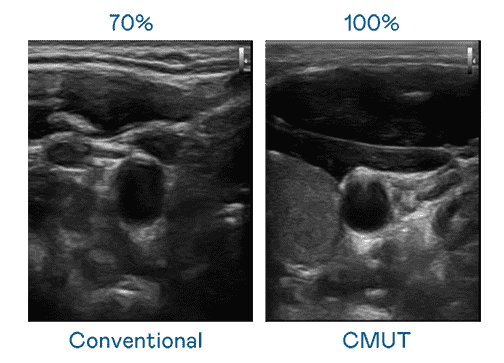

CMUT 技术是一种用电容式微机电元件来产生超音波讯号的技术。。。。与传统 PZT 压电式技术相比,,,CMUT 频宽增加 30%,,,更宽频的超音波讯号让影像解析度大幅提升,,,,是实现高影像品质医疗超音波扫描、、促进精准医疗发展的关键技术。。

大频宽带来超清晰影像

超音波影像的解析度高低,,,首先取决于探头能发出的讯号频宽。。杏悦2 CMUT 可提供高清晰的超音波讯号,,,提供高频宽、、、、高灵敏度、、影像纹理细节更高的超音波影像,,协助医护人员缩短影像判读时间及利用精准的医疗影像进行诊断。。。。